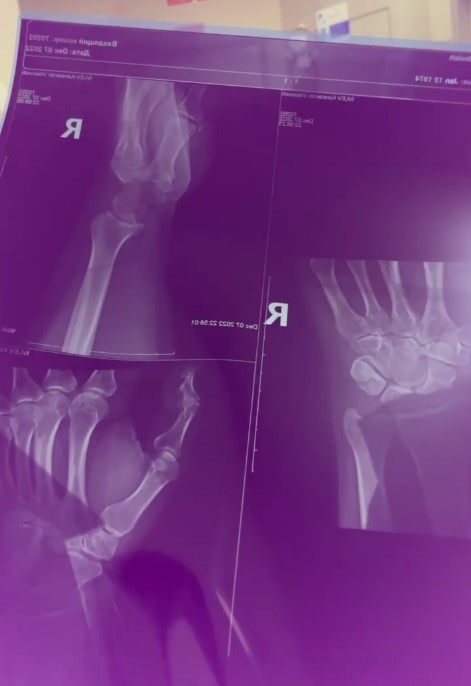

В следующем опубликованном телеведущим ролике показаны рентгеновские снимки его руки. Константин написал, что перелом подтвердился. Больших подробностей о травме он не раскрыл. Не уточнил Ивлев и то, помешает ли перелом съемкам новых выпусков его шоу.